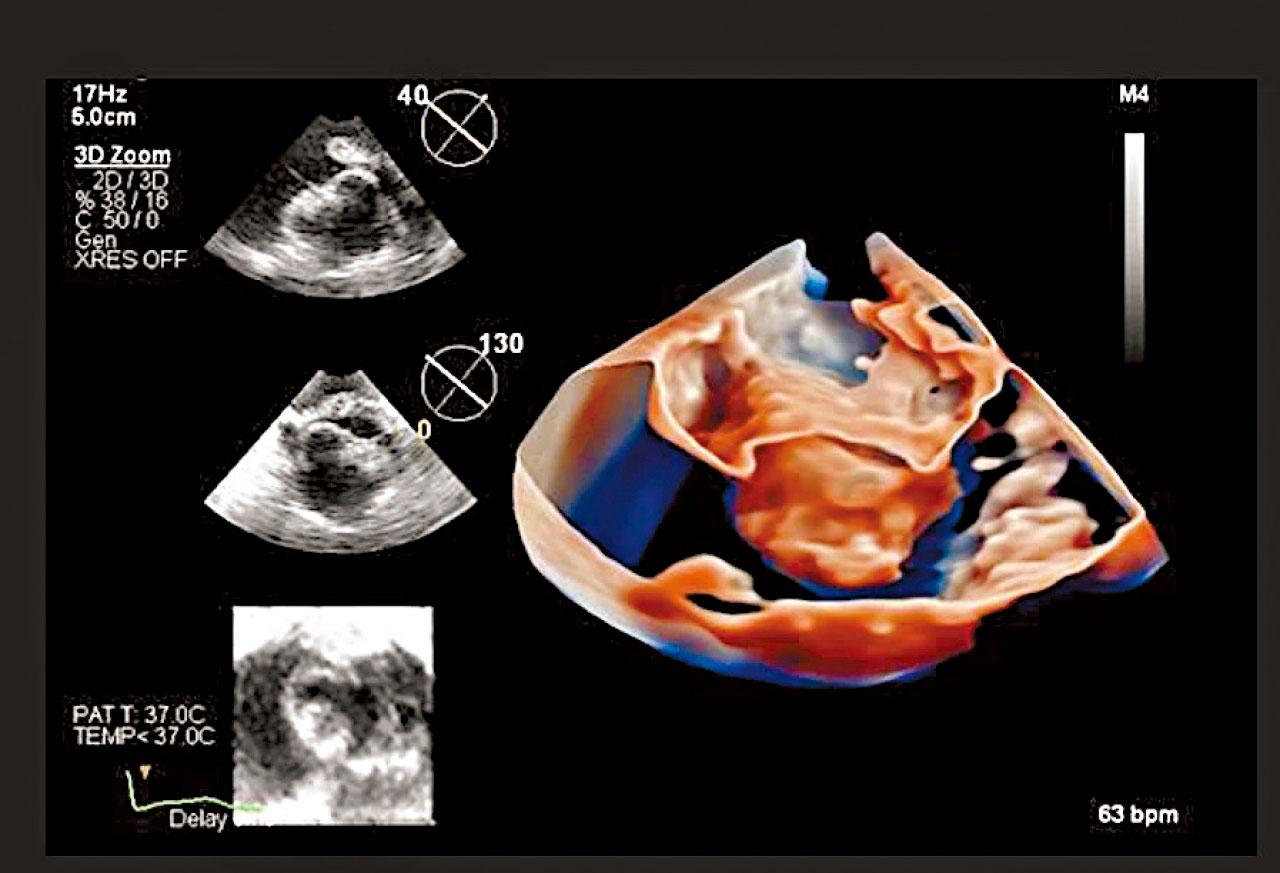

心臟超聲波清晰度大為提升。

高質素3D移動圖像

最新引入香港的4D ICE,可透過導管進入心臟,直接觀察心內結構;而且能夠生成高質素3D移動圖像,即使血流情況亦一目了然。成像質素更高,能提供更仔細的心臟結構細節,有助醫生處理更複雜的個案;左心耳封堵術、二尖瓣修復、三尖瓣置換,以及治療卵圓孔未閉症和心房間隔缺損的手術都可應用。香港港安醫院—司徒拔道心臟科專科顧問醫生鄭長華舉例,「在三尖瓣的手術中,4D ICE便可突破經食道超聲波及以往2D ICE的局限,因為可實時得到更清晰的畫面,在瓣膜抓取(leaflet grasping)過程可更順利。」更重要是患者毋須全身麻醉,減低了手術風險。